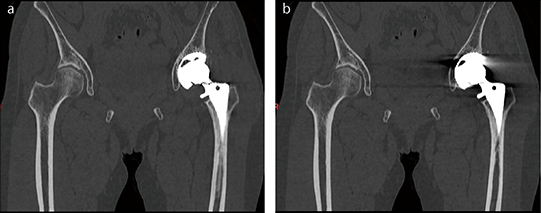

■症例2 人工関節置換術後(左股関節)

a:SEMARあり、b:SEMARなし

金属アーチファクト低減により、骨頭側だけでなくカップ側の骨の評価も可能となる。